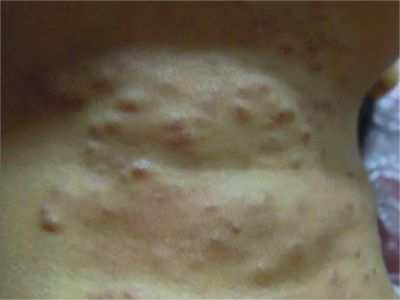

丛状血管瘤又称血管细胞瘤,好发于颈部、躯干等部位,可表现为斑片或斑块,上有血管瘤样丘疹。本病多见于婴儿和儿童,两性相等,大部分为先天性,无自发消退倾向,可以通过激光、冷冻等方式治疗。

丛状血管瘤损害临床表现复杂多变,可以是境界不清楚的红色至紫色浸润性斑块,也可是簇集性丘疹及外生性生长的结节性损害,主要表现为界限不清的暗红色斑片或斑块,其上可有血管瘤样丘疹,出现后逐渐扩大,呈慢性经过,可达5-10cm,然而稳定在一定大小,不再扩大,常伴疼痛与触痛,自然吸收消退概率较小。